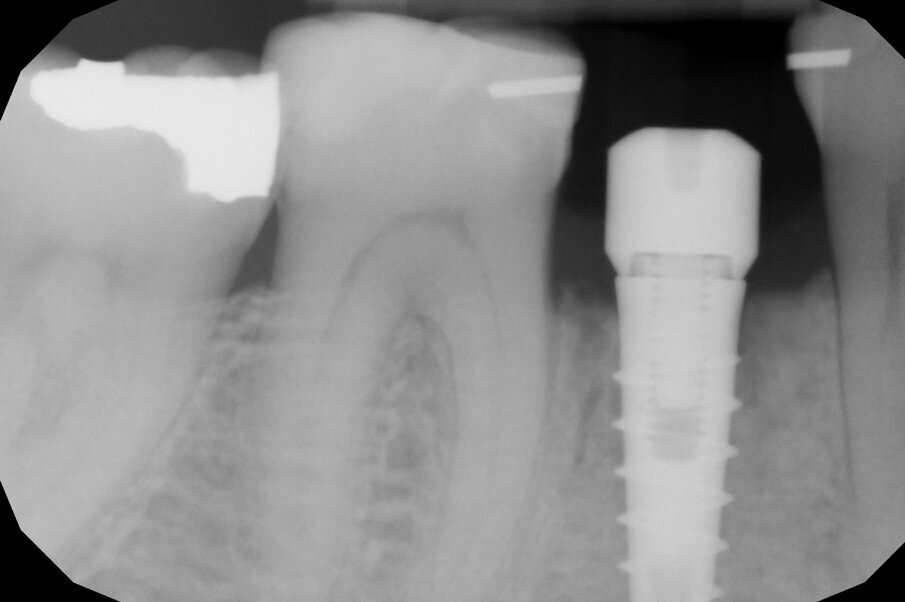

L’estrusione completa del frammento ha richiesto un tempo di 6 mesi, durante i quali è stata modificata più volte l’inclinazione della molla per evitare che il movimento diventasse ortogonale al segmento e mantenere la traiettoria prevista. Così facendo, è stato possibile rigenerare naturalmente l’intero alveolo e inserire, dopo 3 mesi di ulteriore maturazione del tessuto, in un contesto osseo ideale e perfettamente rigenerato un impianto Syra (Sweden & Martina) di diametro 4.25 mm e lungo 11 mm.